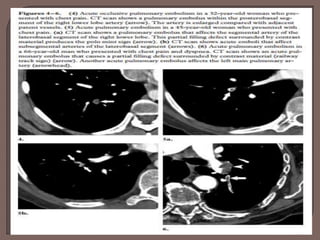

• Complete arterial occlusion with failure to

opacify vessel lumen. Artery may be enlarged

as compared to others of the same order

• Central filling defect surrounded by contrast

producing the “polo mint” sign on images

acquired perpendicular to the long axis of a

vessel and the “railway track” sign on

longitudinal images of the vessel

• Peripheral intraluminal filling defect that

makes an acute angle with the arterial wall